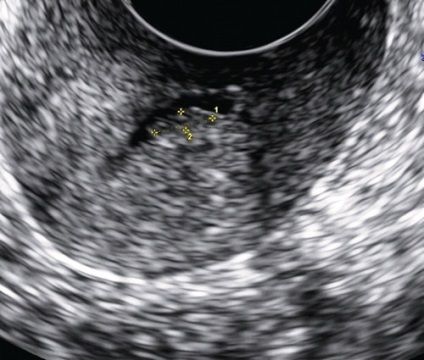

Ez részben annak a ténynek köszönhető, hogy minden esetben a nyaki polipok jellemző a kis méret és egy vereség. Emellett, például a mirigyes polipok általában nem látható ultrahang-letapogatással annak a ténynek köszönhető, hogy nem csak ehonegativnoe mirigyállományt polipok összeolvad a kép a méhnyak és a myometrium lehet megkülönböztethetetlen Ov. Nabotii (ábra. 1), közel az endocervikális, hanem azért is, mert a nyálka a lumen a méhnyak. Ugyanakkor a kép ehonegativnoe folyadék (nyák) hangsúlyozza a kontúrok a visszhang-pozitív kóros oktatás, ami jól látható a hangkép. Mivel van intraluminális polip növekedés és részben lezárja a méhnyakon, fölött vagy alatt a váladék felhalmozódhat, ami megkönnyíti az észlelési az patológiás formáció (ábra. 2). Kétséges esetekben célszerű megismételni a tanulmány periovulyatornoy fázis (késő proliferatív és korai kiválasztó), ha van egy fiziológiai számának növekedése a méhnyak nyálkahártya és közepette anechoic tartalma jól láthatóvá polipok. Folyékony tartalom néha lehetővé teszi, hogy láthatóvá tegyük a polip lába, mint lineáris echogén szerkezet vagy annak szubsztrátja [3, 5]. A átmérője a lumen a csatorna fokozatosan kiszélesedik során proliferatív fázisban, tetőzik ovuláció ideje (1,1 mm között 4-7 nap, és 1,8 mm-es napon 11-14). Miután ovuláció csatornát szűkíti a lumen szinte teljesen (legfeljebb 0,5 mm), a legaktívabb - a korai kiválasztó fázisban [4].

Ábra. 1. Paracervical ciszták eltérő tartalommal ehostruktury.